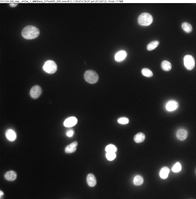

This study represents the first systematic application of the Keyence VHX-7000 platform to characterize CSE-induced morphological changes in HBEpCs. The Keyence system, using uniform LED illumination and HDR imaging, allowed acquisition of detailed, high-contrast images for rapid visualization of cell nucleus outlines against background substrates. HDR processing further enhanced feature visibility, supporting precise cell size quantification from a single wide-field image that captured hundreds of cells at once. Real-time depth composition was utilized to combine multiple focal planes into fully focused composite images, overcoming the challenges of uneven sample surfaces and enabling clear identification of subtle structural changes and damage induced by CSE treatment. This imaging strategy enabled high-throughput, non-destructive, cost-effective assessment across eight experimental groups: 0.3% CSE or 0.3% DMSO across four time points (10, 30, 60, and 90 minutes). Two imaging modes were utilized: Enhanced Contrast and Enhanced Flaw Detection (Figure 2), allowing clear visualization of cellular boundaries and detection of subtle structural alterations.

Quantitative measurement of the long axis of individual cell nucleus was performed using ImageJ and revealed no statistically significant difference in nucleus size between the CSE and DMSO groups at the 10-, 30-, and 60-minute time points (p > 0.05, one-way ANOVA with Tukey's post hoc test). However, as shown in Figure 3, at 90 minutes, CSE-treated cells exhibited a significant change in nucleus size compared to DMSO controls (p = 0.037, one-way ANOVA with Tukey’s post hoc test; n = 25 per group. The mean ± standard deviation values were 16.0 ± 3.23 and 19.6 ± 3.77, respectively). This suggests that prolonged exposure to CSE induces measurable morphological changes in epithelial cells, which are detectable using the Keyence platform.

The ability to efficiently capture and analyze hundreds of cells in a single field of view highlights the Keyence system’s high-throughput advantage. Its HDR and real-time depth composition features proved effective in resolving morphological features even in slightly uneven culture surfaces.

(a) (b)

Figure 2. Keyence Imaging with Enhanced Contrast (a) and Enhanced Flaw (b).

Figure 3. Statistical study of the cell nucleus size using the images captured by VHS 7000. Data are presented as mean ± standard deviation. P values were calculated using one-way ANOVA with Tukey’s post hoc test. n = 25 for each group.